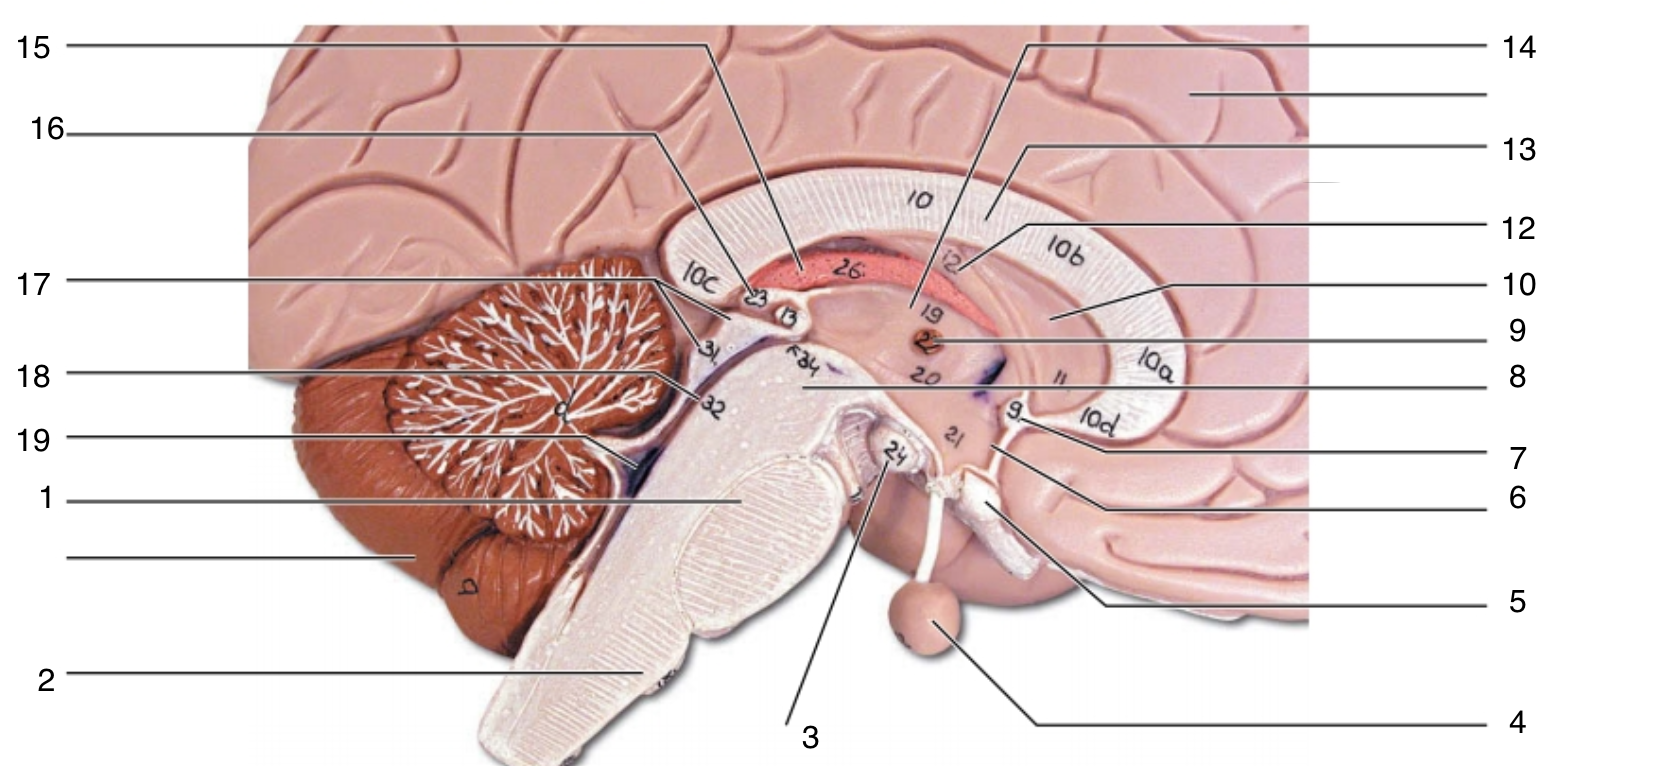

Brain Stem

1

pons

1

2

medulla oblongata

2

3

mammillary body

3

4

pituitary gland

4

5

optic chiasma

5

6

hypothalamus

6

7

anterior commissure

7

8

midbrain

8

9

interthalamic adhesion

9

10

septum pellucidum

10